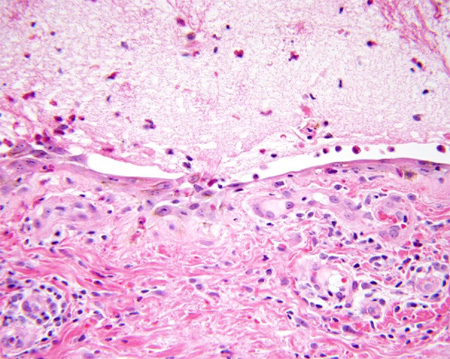

Penfigoide bolhoso

Fibrinas e eosinófilos presentes na cavidade da vesícula

Do acervo da Dra. Vesna Petronic-Rosic